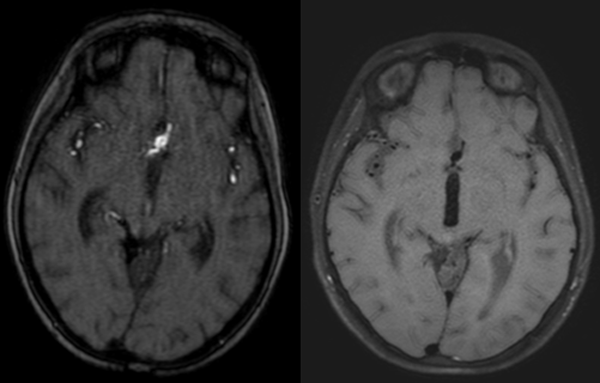

Dos años más tarde, en control por Infectología, refirió cefalea holocraneana pulsátil de moderada intensidad, asociada a mareos, náuseas y vómitos esporádicos. Se solicitó una nueva angioRM, la que arrojó un aneurisma fusiforme de la arteria comunicante anterior con compromiso del segmento A2 izquierdo e irregularidad asociada de M1 derecho (Figuras 3 y 4). Ante estos hallazgos se efectuó angiografía cerebral con colocación de un diversor de flujo, angioplastia con balón y embolización con “coils”.

Figura 3. RM cerebral, secuencia blackblood: dilatación aneurismática de 8.1 x 5.9 mm en el segmento comunicante anterior e irregularidad con reducción de calibre en M1 derecho. La técnica suprime la señal de la sangre en movimiento, haciendo que la luz vascular se observe negra y permitiendo resaltar la pared arterial.

Figura 4. Angiografía digital cerebral, reconstrucción 3D: se observa dominancia de la ACA derecha con pasaje a través de la ACoA hacia la ACA izquierda. A nivel de la ACoA se identifica un aneurisma fusiforme que compromete toda su longitud y se extiende hasta el extremo proximal del segmento A2 izquierdo. Del domo aneurismático emerge una rama arterial.